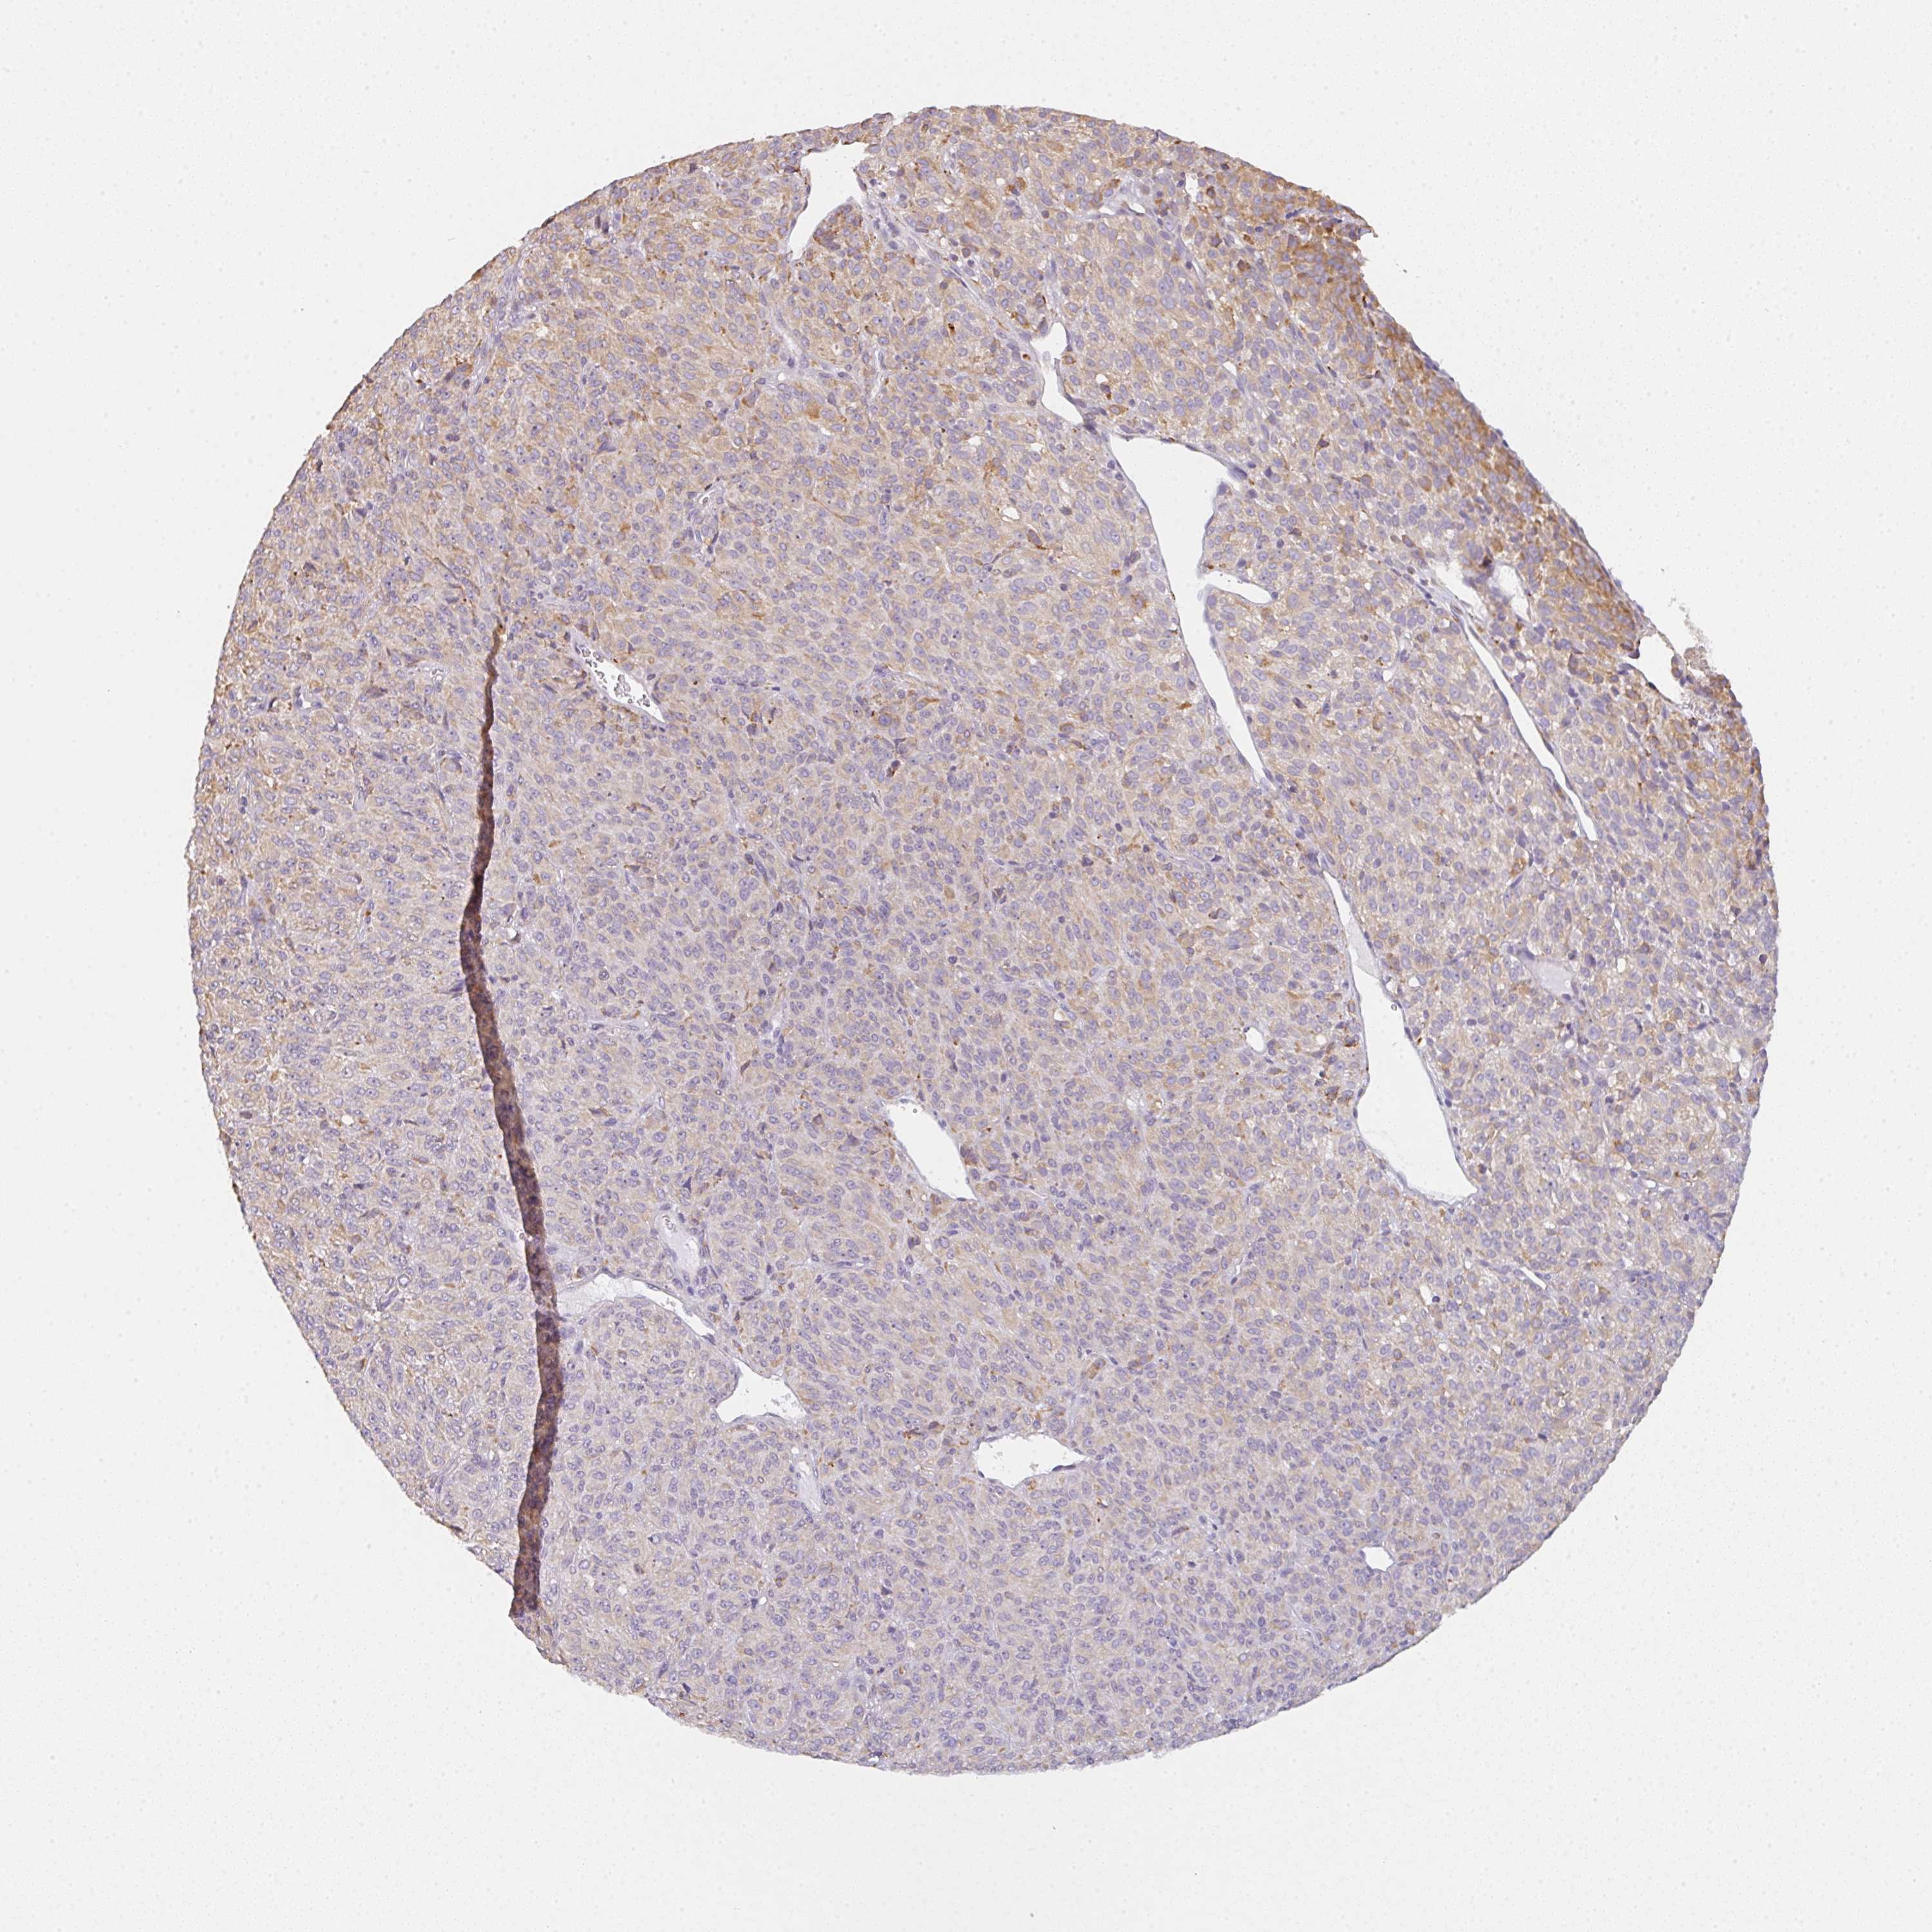

MELANOMA - Protein expressioni

A mouse-over function shows sample information and annotation data. Click on an image to view it in a full screen mode. Samples can be filtered based on level of antibody staining by selecting one or several of the following categories: high, medium, low and not detected. The assay and annotation is described here.

Note that samples used for immunohistochemistry by the Human Protein Atlas do not correspond to samples in the TCGA dataset.

Antibody stainingi

Antibody staining in the annotated cell types in the current human tissue is reported as not detected, low, medium, or high, based on conventional immunohistochemistry profiling in selected tissues. This score is based on the combination of the staining intensity and fraction of stained cells.

Each image is clickable and will lead to virtual microscopy that enables deeper exploration of all samples and also displays staining intensity scores, fraction scores and subcellular localization as well as patient and tissue information for each sample.

Antibody HPA055849

Staining

High

Medium

Low

Not detected

Intensity

Strong

Moderate

Weak

Negative

Quantity

>75%

75%-25%

<25%

None

Location

Nuclear

Cytoplasmic/membranous

Cytoplasmic/membranous,nuclear

Malignant melanoma, NOS

Malignant melanoma, Metastatic site